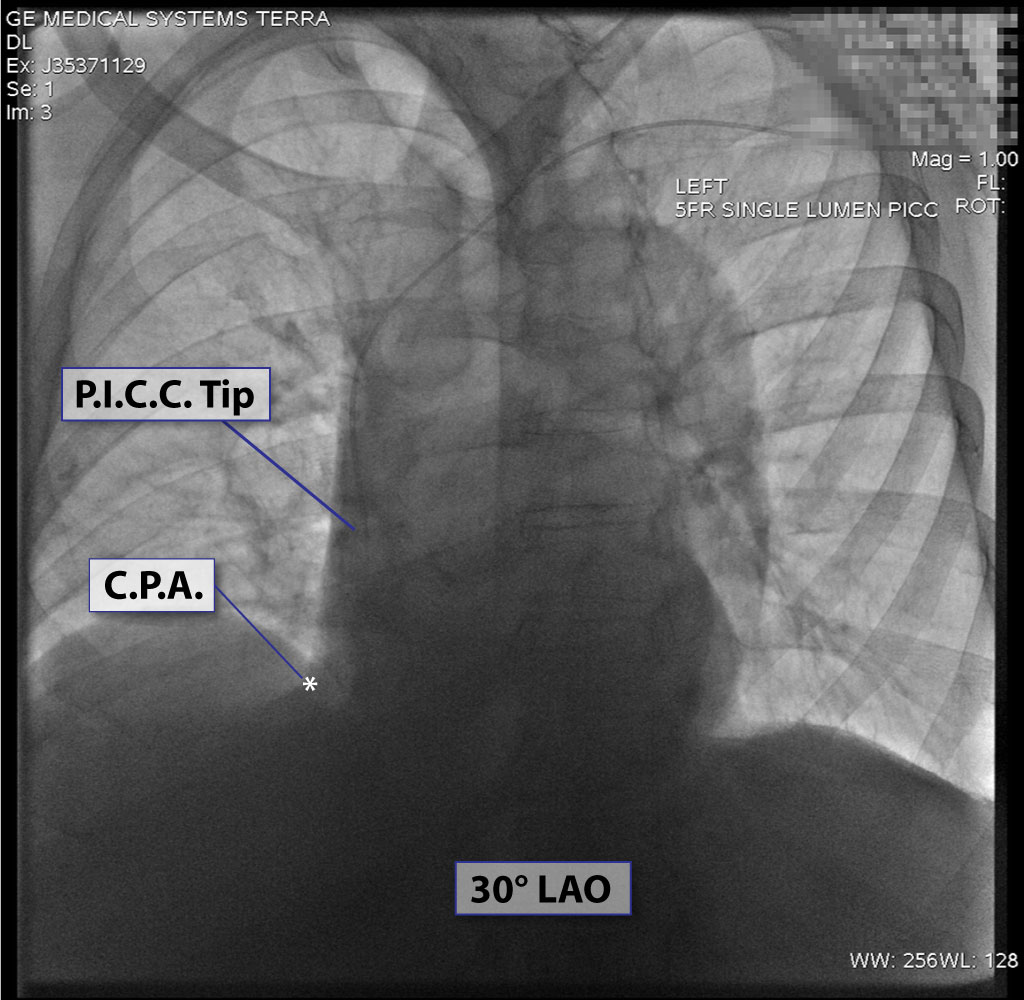

3. Chest x-ray rotation tissues: Not infrequently, the chest x-ray will be rotated causing the right cardiac margin to deviate from its normal AP appearance. In such situations, depending on the degree of rotation, an estimation of the SWEET SPOT™ is all that may be possible. In such circumstances, the right cardiophrenic angle is the most reliable anatomic landmark. Since the right atrium is immediately cephalad to a normally positioned right cardiophrenic angle, a reliable estimation of acceptable catheter tip location is still possible. The height, and consequently the width of the rectangular Sweet Spot™ box will be less exact and therefore a relatively short catheter tip position may require a non- rotated chest x-ray to confirm an acceptable location. Aim for the right atrium. See Figs. T.1, T.2, and T.3.

17. “A good use of carinal landmarks for catheter tip location- right sided White Out.” See Fig. T.4 - Carina.